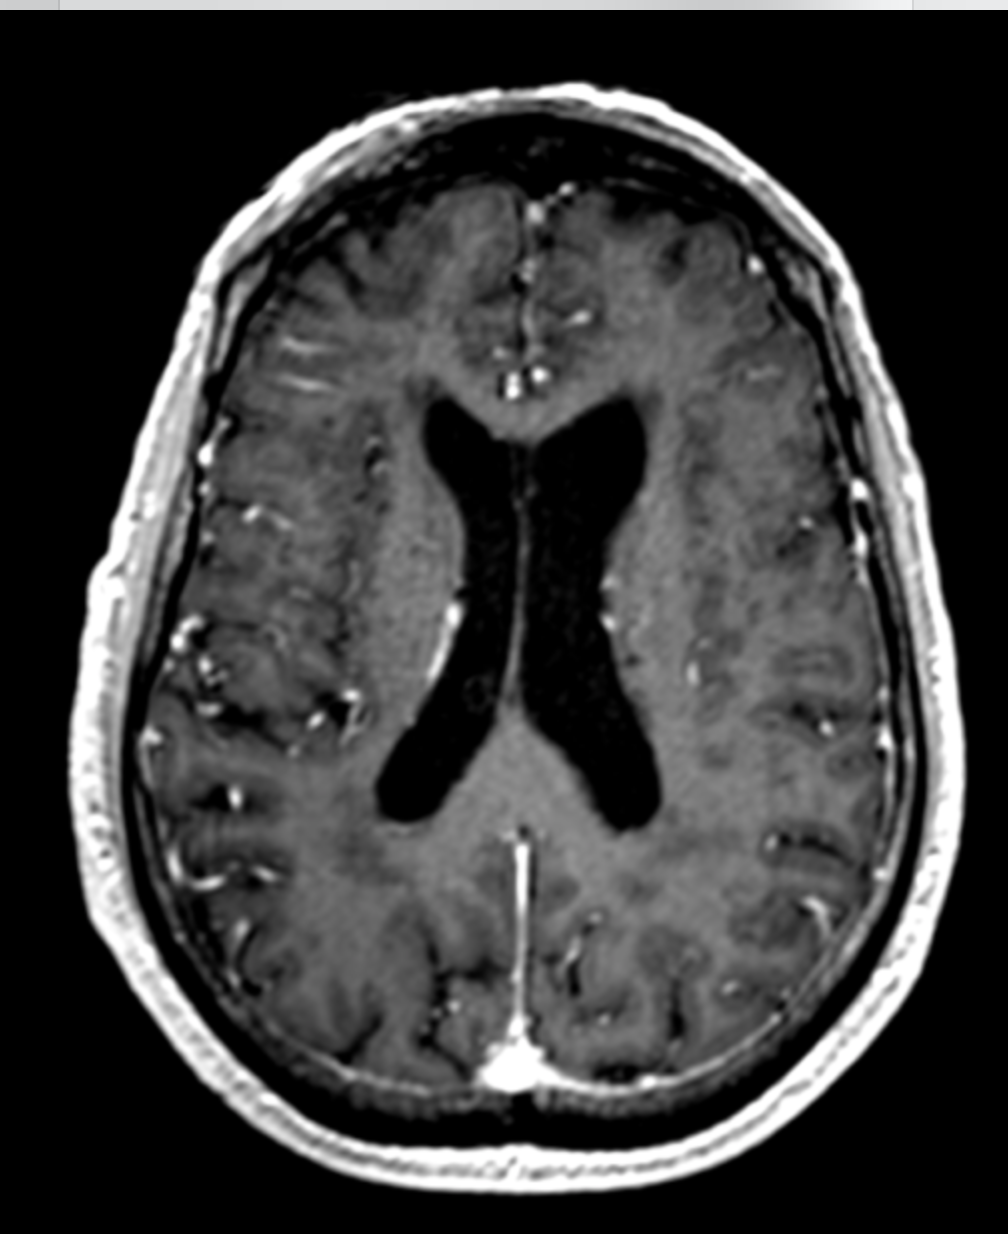

Quelle est la séquence de cet IRM ?

T1 Gado